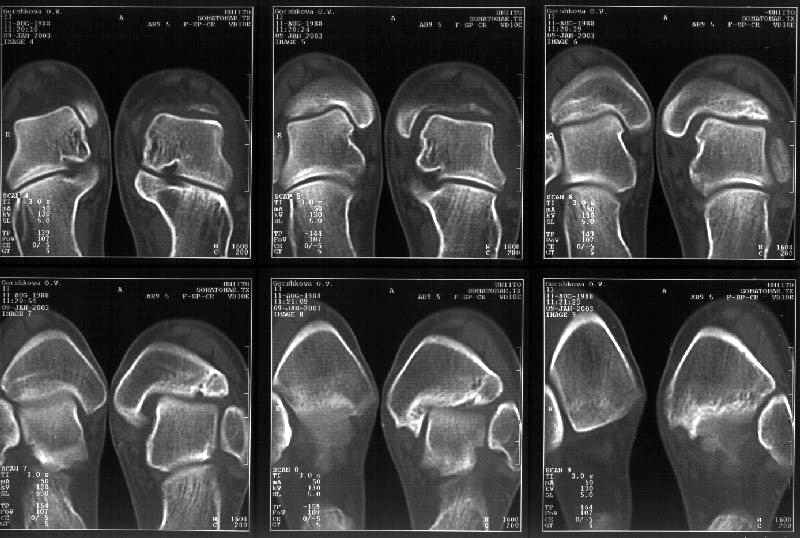

Мне в тоже время совершенно ясно видно по той же КТ, по 4 срезам, расположенным в центре и вверху пленки, что перелома внутренней лодыжки не было, в следующем собщении я приложу увеличенный фрагмент томограммы. А к этому письму прилагаю увеличеный фрагмент послеоперационной рентгенограммы, где выделил отколотый фрагмент

позади внутренней лодыжки. И он, как я вижу, находится между стержнем и тараном. А перелома внутренней лодыжки, и тем более смещения, IMHO

не определяется.

Отправитель: Alexander Chelnokov 12 Январь 2003, 14:55

> направлениях.Отдавил и отломал переднюю часть мед. маллеолюса от его

> тибиальной основы. По мне, КТ это совершенно ясно показывает.

Здесь 4 среза, начиная от основания лодыжки и проксимальнее. Где, по Вашему мнению, проходит линия перелома, отделяющая переднюю часть внутренней лодыжки от большеберцовой кости? Заранее спасибо.

Кликните для загрузки файла get_image.jpg

38KB (39385 bytes)